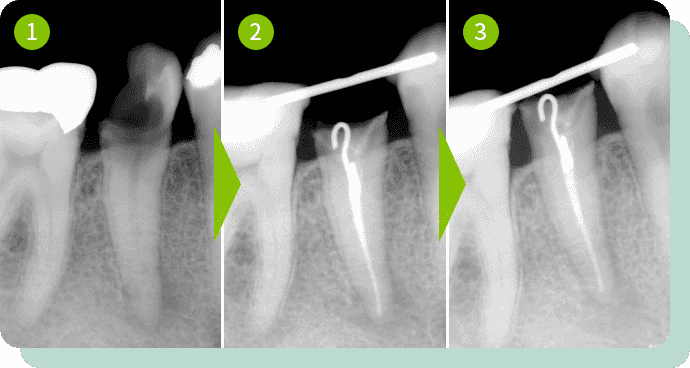

挺出した例

歯を動かすことで、

歯を残せるケースもあります

むし歯が歯茎の下、歯を支える骨に至るまで進んでしまった場合は抜歯をせざるを得ない場合も多々あります。

そのような場合、このケースのように矯正的に歯を上に引っ張り上げることによりなんとか歯を残せるケースもあります。

残せる可能性のある歯は積極的に残していきましょう。

リスク・副作用:疼痛、出血など

費用:矯正及び歯周外科治療55,000円